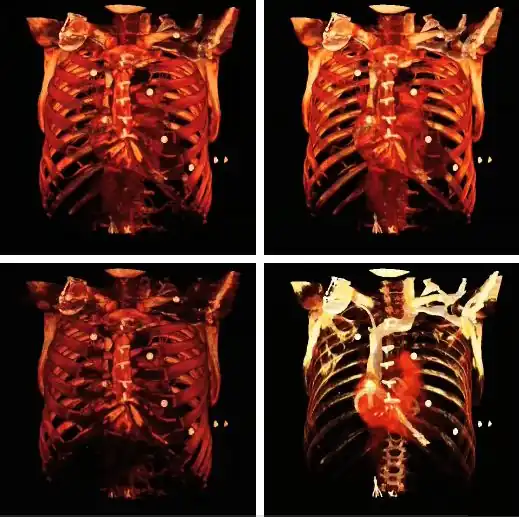

A final feature to note about volume rendering is that 3D editing techniques can be applied so as to exclude unwanted features from the computations and to expose internal structure. This is illustrated in the following figure, where planes of an orthogonal frame can be moved to crop the voxel data from six directions.